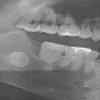

プレート除去だけなので、あっさり復活

前回の切除手術では5日後にやっと IP 接続だったけど、今回はプレートの除去だけだったこともあり、術後翌日である今日から早速 IP 接続。

プレート除去のための切開によって右下顎部分が炎症を起こして腫れている&腫れ防止の圧迫処置をしていることから、あまり口を開けられないにも関わらず、今日の朝食から経口摂取の普通食(但し御粥)だったりと、なかなかにサディスティクな治療計画。